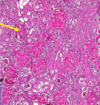

Stomach, Signet Ring Carcinoma

Invasion by MALIGNANT TUMOR composed of signet ring cells. These cells are poorly cohesive and have clear cytoplasm with dark eccentric nuclei

Malignant

Signet ring cells

Due to cytoplasmic mucin pushing nucleus to side